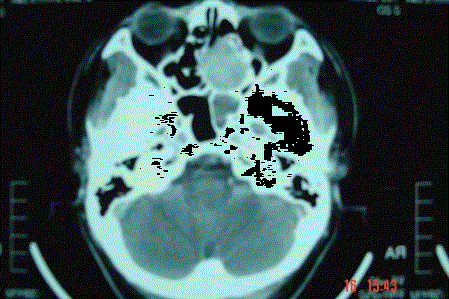

问题 病历摘要: 患者男,37岁,因右鼻塞伴涕中带血4个月入院,患者4个月前始右鼻塞,为间断性,偶有涕中带血,时有流脓性分泌物,并症状渐渐加重。但发病以来患者无头痛、面部麻木和疼痛,无复视及流泪,张口正常。检查:右侧鼻腔总鼻道可见表面光滑、质中、粉红色肿物,触之不易出血。鼻咽黏膜光滑,未见新生物和黏膜糜烂。颈部未及淋巴结肿大。 对于较大的肿瘤,为减少术中出血,下列哪些方法正确?